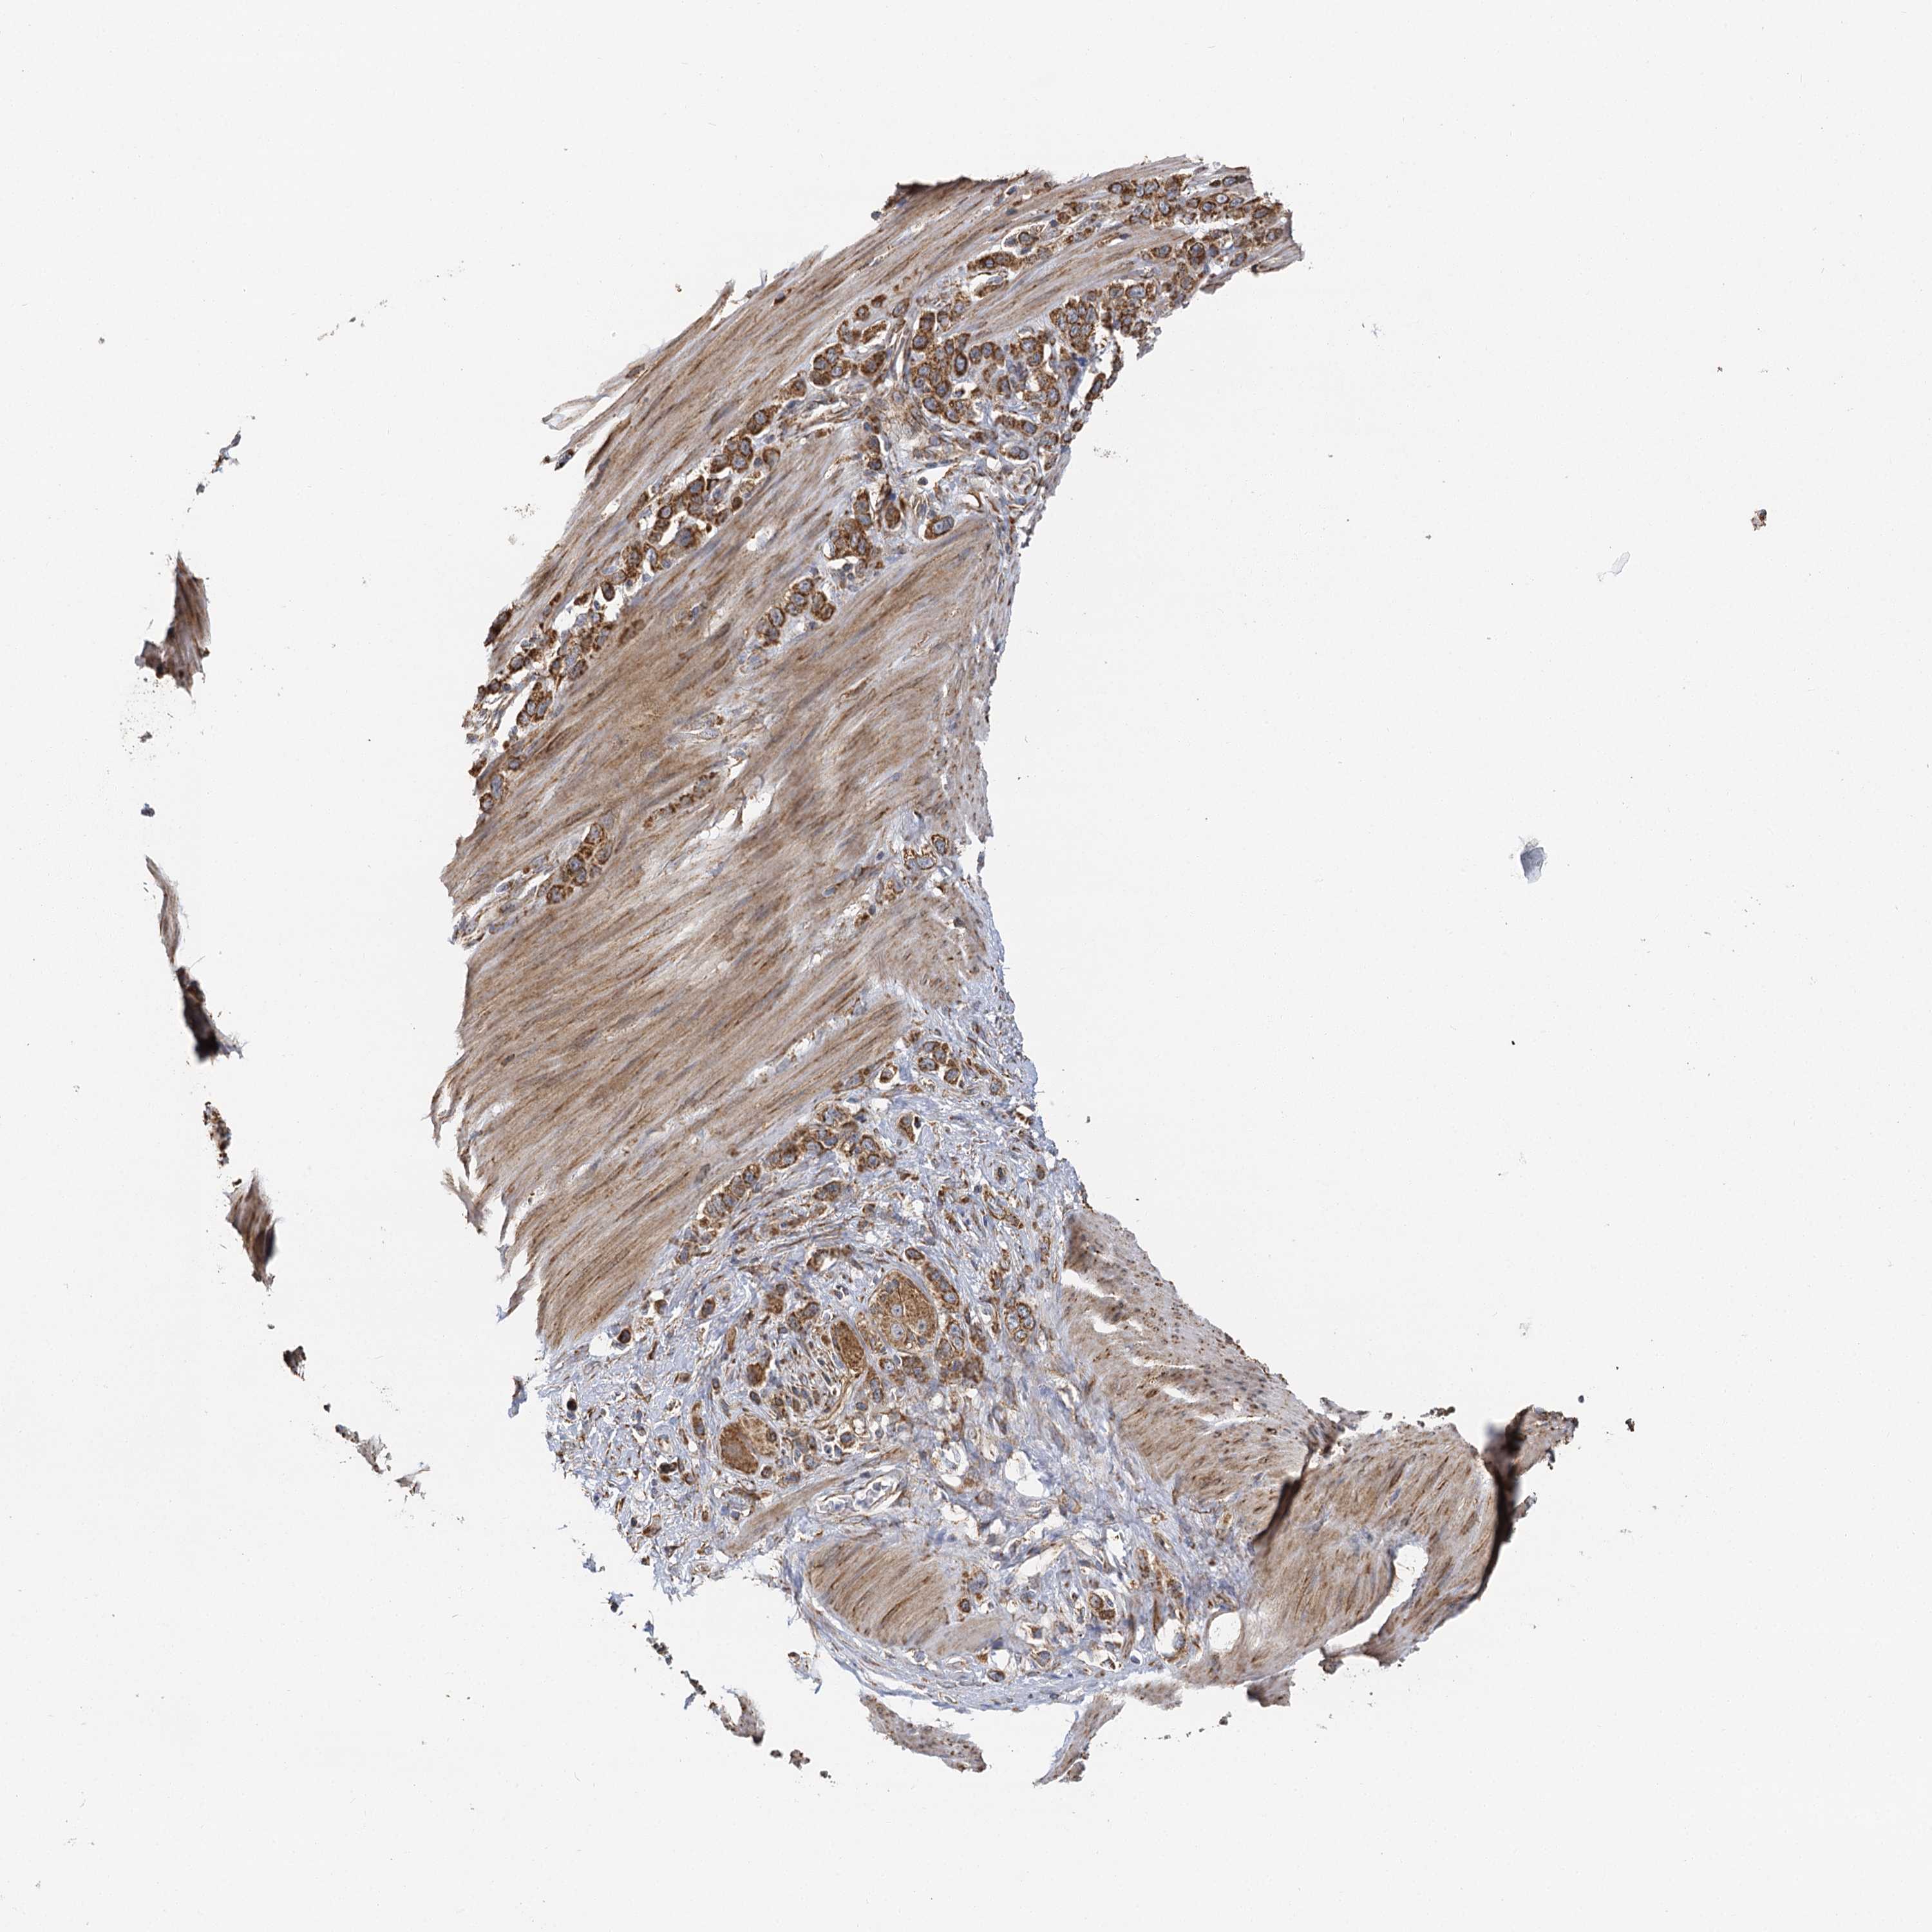

STOMACH CANCER - Protein expressioni

A mouse-over function shows sample information and annotation data. Click on an image to view it in a full screen mode. Samples can be filtered based on level of antibody staining by selecting one or several of the following categories: high, medium, low and not detected. The assay and annotation is described here.

Note that samples used for immunohistochemistry by the Human Protein Atlas do not correspond to samples in the TCGA dataset.

Antibody stainingi

Antibody staining in the annotated cell types in the current human tissue is reported as not detected, low, medium, or high, based on conventional immunohistochemistry profiling in selected tissues. This score is based on the combination of the staining intensity and fraction of stained cells.

Each image is clickable and will lead to virtual microscopy that enables deeper exploration of all samples and also displays staining intensity scores, fraction scores and subcellular localization as well as patient and tissue information for each sample.

Antibody HPA013162

Antibody HPA036652

Antibody CAB032830

Staining

High

Medium

Low

Not detected

Intensity

Strong

Moderate

Weak

Negative

Quantity

>75%

75%-25%

<25%

None

Location

Nuclear

Cytoplasmic/membranous

Cytoplasmic/membranous,nuclear

Adenocarcinoma, NOS

Adenocarcinoma, High grade